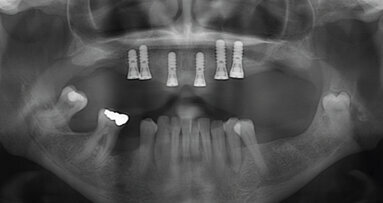

S Acurisem je léčba implantáty stejná jako obvykle, až na fázi konečné protetiky. To je bod, kdy se vše stává jednodušším a lehčím a zároveň si stále drží výsledky, které si zubní lékaři a pacienti přejí. Vybavení Acuris obsahuje abutmenty s různými angulacemi pro všechny implantační systémy od Dentsply Sirona Implants3 a plnou sadu kapen a nástrojů. To dělá Acuris vhodným pro jednočlenné korunky na všech pozicích.

Digitální pracovní postupy mohou zlepšit výsledky naší léčby. V této kazuistice je prezentováno multidisciplinární ošetření pacienta se ...